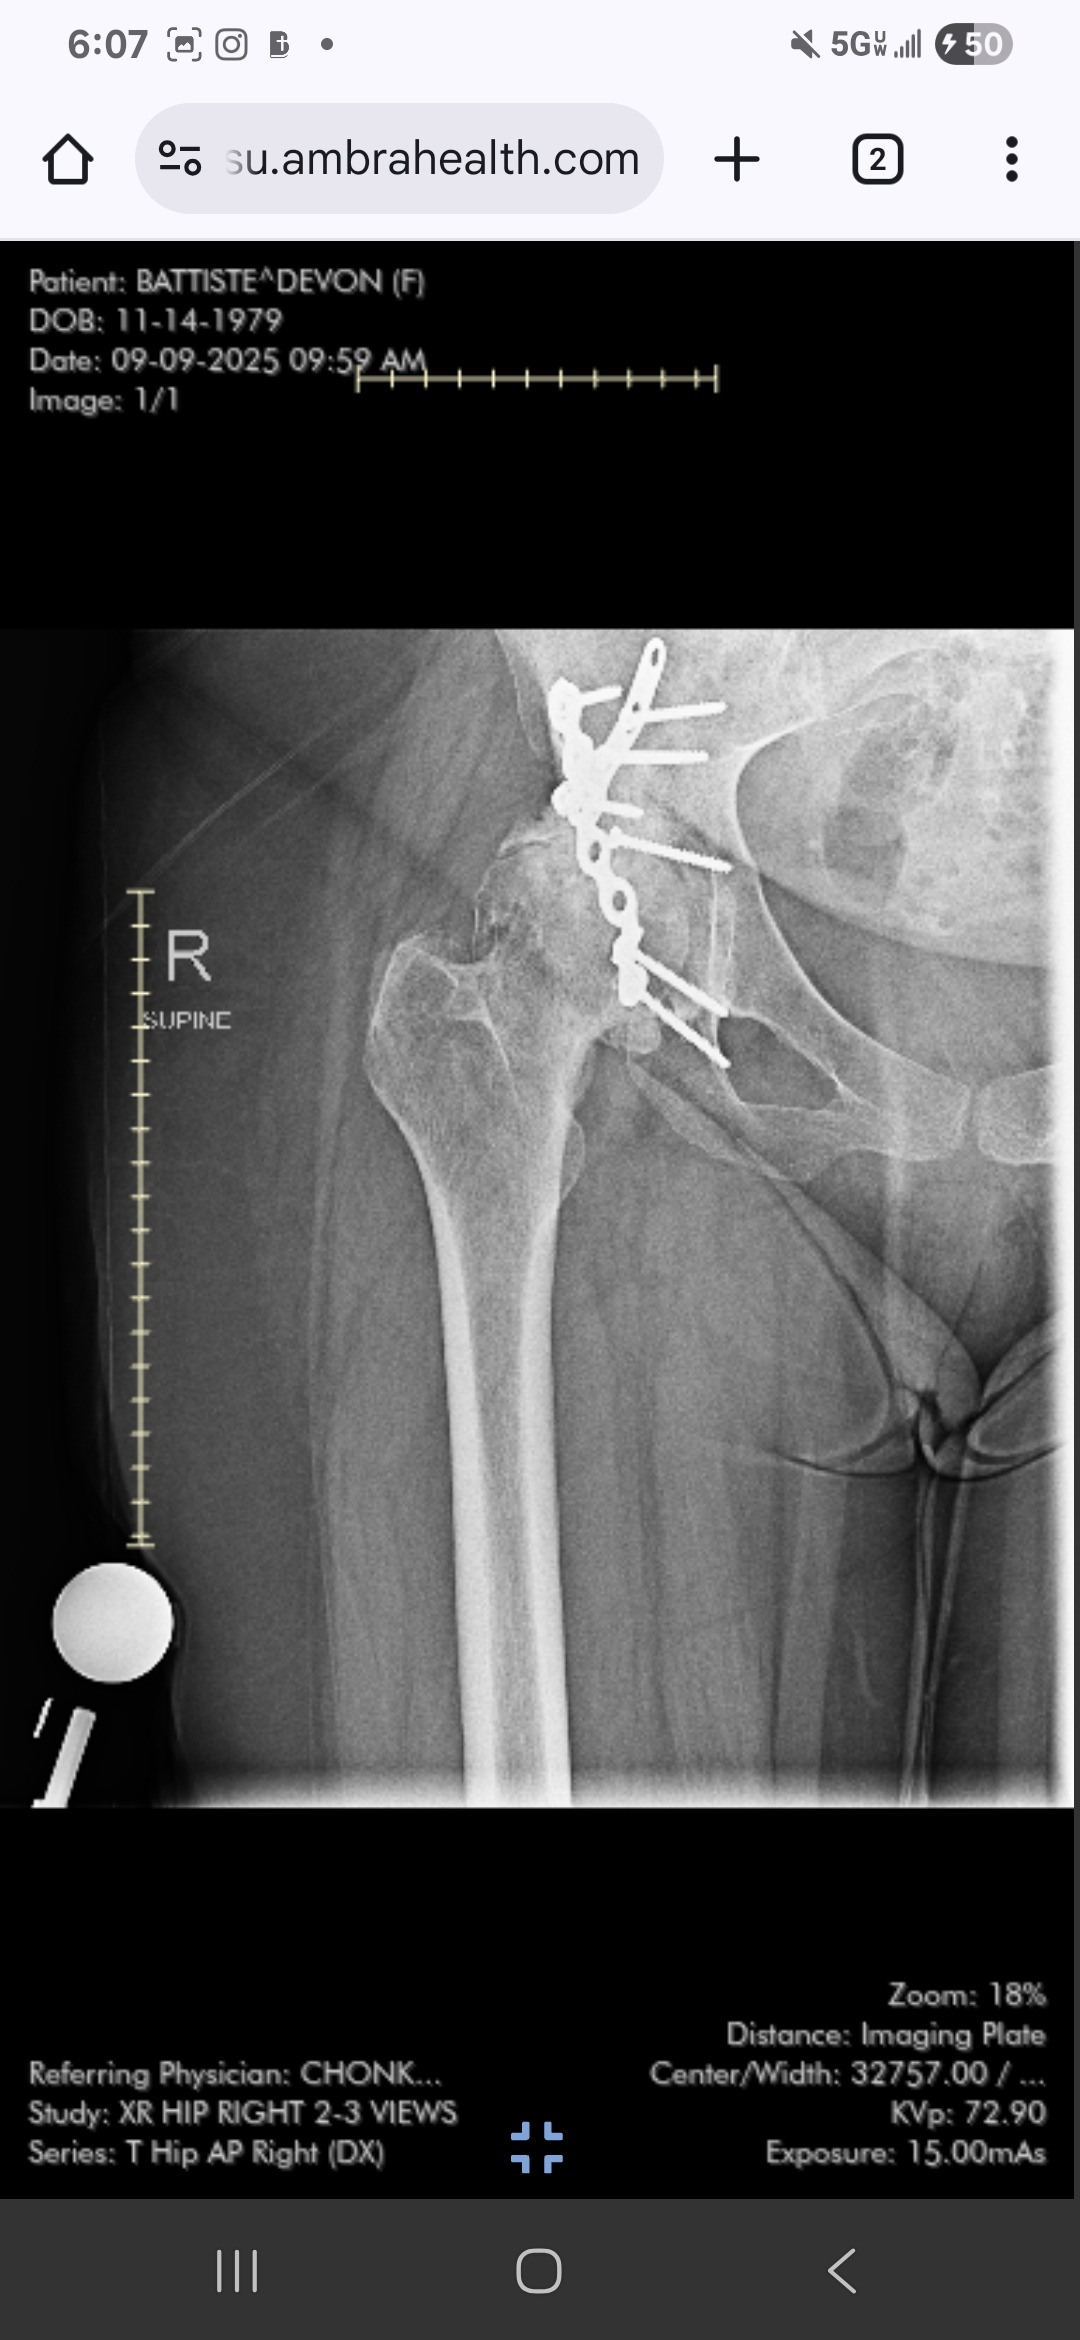

Now, I am facing another major hurdle: I need a total hip replacement due to an accident that happened twenty years ago, which has left me with severe post-traumatic arthritis. Unfortunately, because this is considered an outpatient surgery, my health insurance will not cover the cost of a rehabilitation center where I could recover safely. The space where I currently stay is simply too small for me to heal properly, and I need my own personal space—perhaps an extended stay hotel or Airbnb—for a few weeks after surgery. I just don’t have the means to cover these costs right now, and I am reaching out for support.